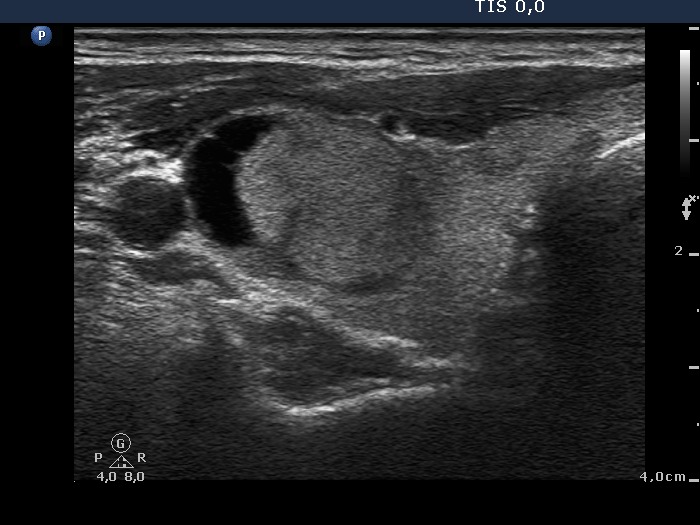

Clinical presentation: A 49-year-old man was referred for an evaluation. He had upper airway infection lasting for 3 months. On ultrasound, an enlarged lymph node in the right side of the neck and a cystic nodule in the thyroid were discovered.

Palpation: an elastic nodule in the right lobe and a firm lymph node lateral to the right lobe.

Ultrasonography. There was a mixed echonormal-cystic nodule in the upper pole of the right lobe. Multiple hypoechogenic smaller lesions were also found in this lobe. Lateral to the thyroid there was an enlarged lymph node with hyperechogenic areas and increased vascularization.

Cytological report: malignant tumor corresponding to metastasis of a small cell lung cancer (both from the small hypoechogenic lesion in the right thyroid and from the lymph node).